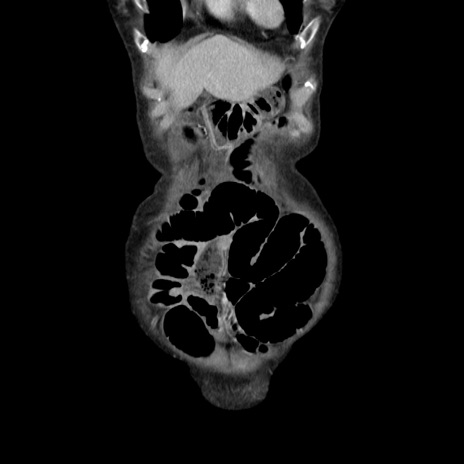

症例25(冠状断像)

症例

【症例】80歳代女性

【主訴】胸のつかえ感

【現病歴】約9時間前に食後から胸のつかえた感じあり、嘔吐あり、来院。

【既往歴】胃癌(全摘)、胆摘、虫垂炎

【身体所見】心窩部に圧痛あり、反跳痛なし。

【データ】WBC 5700、CRP 0.05